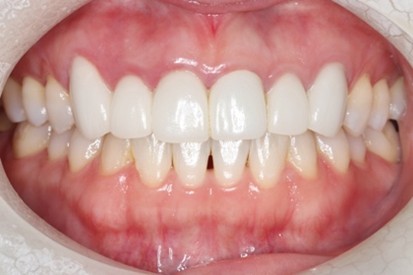

Before

下顎前歯に顕著な歯肉退縮を認める

切開はEPPT(entire papilla preservation technique)

After

手術後4年経過

歯周基本治療後に根面被覆術を実施しその後はメンテナンス

歯肉退縮が生じることで知覚過敏に繋がるケースは少なくない。また将来的には根面う蝕の可能性も高くなるため、歯肉退縮している場合には予防的な観点から根面被覆手術をした方がいい場合がある。特に知覚過敏が強い場合にはブラッシングがしづらい場合も多くよりう蝕や歯周病のリスクが上がるため注意が必要と考える。